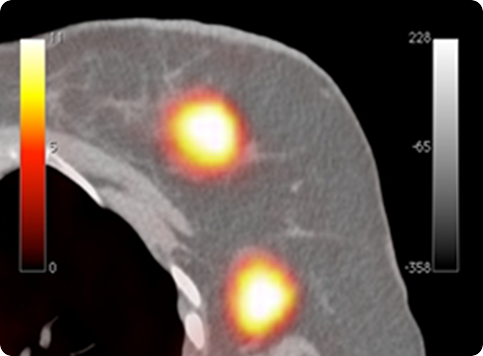

PETsys has developed two PET prototypes based on APD-based detector modules which target breast cancer applications (Clear PEM System).

PETsys and the R&D Consortium were invited by CERN to join the Clear-PEM Sonic project combining PET with Ultrasounds, in the framework of the Crystal Clear Collaboration for detection of early stage breast cancer. We have developed the first integrated PEM-Ultrasound system with Elastography capabilities, the Clear-PEM Sonic prototype, along with SuperSonic Imagine. This system is now being tested at Ospedale San Gerardo in Italy after being used in a series of clinical tests at Hospital Nord in Marseille.

Due to its very good spatial resolution and accessibility of the Field-of-View, the Clear-PEM system can also be used for small animal imaging.